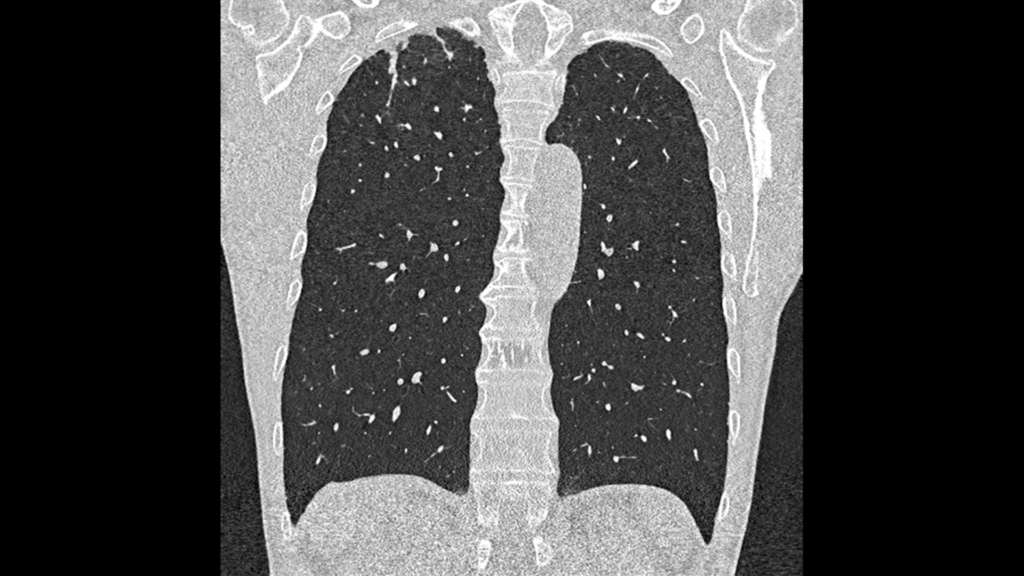

TC con conteggio di fotoni in pneumologia

La massima risoluzione, la ridotta esposizione alle radiazioni e le informazioni spettrali intrinseche sono la base per una valutazione senza compromessi di pazienti vulnerabili con malattie polmonari.